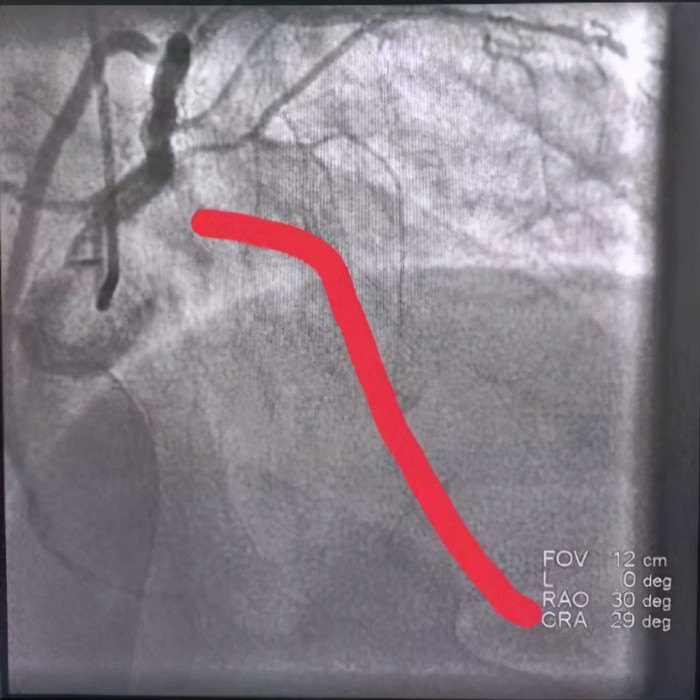

在患者被推到导管室门口 , 患者心脏再次室颤 , 医生再次电击除颤;这时候导管室早在20分钟前做好了一切手术准备 。 患者造影很顺利 , 造影显示心脏做大血根部堵塞 , 经过导丝通过 , 球囊扩张 , 血流显影 , 支架植入 , 血流恢复 。

手术后